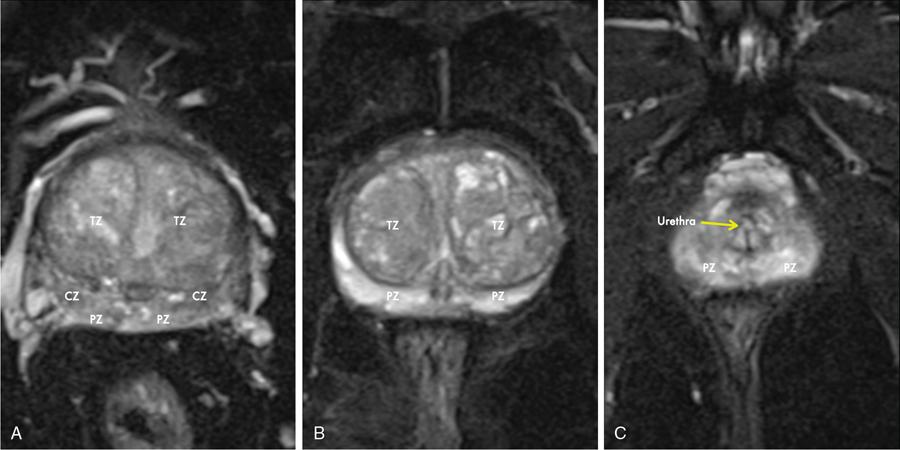

Karthik Ganesan, Disha Lokhandwala, Ujjwal Bhure, Jay Mehta Morphogenesis of the male genitourinary system is governed by the coherent interaction of three units, namely the Wolffian duct, urogenital sinus and foetal gonads. The Wolffian ducts are the embryonic precursors of the male internal genitalia, arising in the anterior intermediate mesoderm at 4 weeks of gestation. They elongate as a cord of cells that caudally extend to the urogenital sinus. Between 5 and 8 weeks of gestation, the urorectal septum divides the cloaca into a ventral compartment, which forms the urogenital sinus, and a dorsal compartment, which forms the rectum. The gonads form as epithelial thickenings on the ventromedial surface of the mesonephros and produce testosterone at 8 weeks of gestation, reaching a peak at 10–15 weeks. Under the effect of testosterone produced by the foetal testis, the prostate anlage forms at the tenth week of gestation. Precursor of the anlage begins with proliferation of solid epithelial buds from the epithelium of the urogenital septum into the adjoining mesenchyme in response to interaction of 5α-dihydrotestosterone with mesenchymal androgen receptors. As growth progresses, solid cords of epithelial cells are formed, growing into the mesenchyme in a specific three-dimensional arrangement (establishes the lobar divisions of the prostate gland). These solid cords develop a central lumen at birth and are lined by a layer of flat basal epithelium and a luminal layer of tall columnar secretory epithelium. Mesenchymal component forms the stroma, which has a large proportion of smooth muscle. Postnatally, the epithelial cords continue to arborize till puberty without any change in volume or glandular architecture. Although the foetal prostate has been described to have a histologically distinct peripheral zone (PZ) as early as 12 weeks of gestation, the mature zonal anatomy develops in concordance with the androgen surge at puberty. The most commonly utilized ultrasonographic technique for the evaluation of the prostate is via a suprapubic approach. The abdominal transducers used in this approach are relatively low frequency and while it offers the advantage of greater depth of penetration without intracavitary probe insertion; however, it does not depict the zonal anatomy and its chief application lies in volume estimation. Hence, transrectal ultrasonography (TRUS) completely outweighs the transabdominal approach in terms of depicting zonal anatomy, visualizing and localizing small lesions, demonstrating vascularity and performing biopsies. TRUS is performed using high frequency transducers (5–7.5 MHz) to optimize soft tissue resolution. An enema is administered 1 h prior to the examination to clear the field of insonation. Patient is positioned in left lateral decubitus, with knees bent toward the chest and ideally a digital rectal examination (DRE) is conducted prior to probe insertion. The transducer is first draped with a sterile barrier and lubricated, After insertion, the barrier is filled with 40–50 cc of water, making sure that no air enters. On completion, water is aspirated and the probe is withdrawn. The gland is initially scanned in the axial plane from the base to the apex, beginning at the level of the seminal vesicles, and the probe is gradually withdrawn to view the entire glandular parenchyma in axial sections up to its caudal aspect. This approach allows a cursory evaluation of glandular symmetry as both halves of the prostate can be evaluated simultaneously. Subsequently, sagittal views are acquired by rotating the probe across the transverse span of the gland, demonstrating the seminal vesicles, midline gland (visualizing both the apex and the base), with sequential scanning up to the contralateral margin of the gland. Sonographically, the prostatic capsule is seen as a smooth well-delineated, hyperechoic structure. With the newer ultrasound systems, the zonal anatomy can be delineated by TRUS; PZ appears echogenic relative to the central zone (CZ) and the transition zone (TZ), which are hypoechoic in juxtaposition (Fig. 11.12.1). Anterolaterally, the preprostatic venous plexuses are seen as anechoic tubular structures with intervening echogenic preprostatic fatty tissue. Glandular volume is estimated using an ellipsoid formula by obtaining the maximum anteroposterior, superoinferior and transverse dimensions and multiplying their product by π/6. Colour Doppler imaging is utilized to illustrate vascularity, as majority of the normal prostatic tissue (excluding the neurovascular bundles [NVBs] and pericapsular and periurethral regions) has symmetrical but sparse flow and an increased microvessel density raises the suspicion of prostatic carcinoma. However, the appearances of prostatic carcinoma can be variable on colour Doppler imaging, ranging from focal increase in vascularity around a nodule to an asymmetric increase in size and number of vessels on the affected side and conventional Doppler has found to elevate specificity by about 5%–10%. Additionally, Doppler imaging has also demonstrated some utility in distinguishing fibrotic tissue from local recurrence. However, vessels supplying cancerous tissue are of the order of 10–50 μm, which is well below the 1-mm resolution limit of conventional Doppler techniques. Contrast-enhanced colour Doppler imaging overcomes this limitation and facilitates imaging of microvessels, using intravenously administered microbubbles (less than 10 μm diameter) of an inert gas (sulphur hexafluoride) with a lipid or galactose shell, allowing quantification of blood flow in the cancerous microvessels. Additionally, these microbubbles act as vascular tracers and by monitoring the passage of a bolus injection through the tissue of interest, time–intensity curves are created. This permits the formulation of functional indices, including bolus arrival time, time to peak intensity, area under the curve and wash-in/wash-out curves. These indices can further extrapolate functional images, on a pixel-by-pixel basis, overlaid on grey-scale images. Quantitative methods to demonstrate perfusion are based on the destruction of microbubbles by high-power ultrasound pulses, and then observing the rate of microbubble replenishment in the field of interest to calculate flow rate. Halpern et al. utilized contrast-enhanced ultrasound and intermittent harmonic imaging with power Doppler, and exhibited an increment in sensitivity from 38% to 65% with a specificity of 80% in prostate cancer detection. Cadence contrast pulse sequencing (CPS) is a low-power multipulse imaging technique utilizing pulses with variable amplitudes and phases followed by a summation of the resulting echoes, permitting tissue suppression, allowing detection of even a small amount of contrast agents retained in the tissues. Real time elastosonography evaluates and quantifies tissue stiffness (Young’s modulus) by measuring strain under an applied stress (transducer compression) and maps areas of variable stiffness in colour-coded and grey-scale images simultaneously and shows potential in improving prostatic carcinoma detection. In a study comparing elastography and T2-weighted (T2-w) endorectal magnetic resonance imaging (MRI), similar sensitivity rates and negative predictive values (NPVs) were attained in the detection of prostatic carcinoma. Prostate gland is an inverted cone-shaped subperitoneal retropubic gland, with its base located rostrally and apex located caudally. The base is attached to the bladder neck and the apex sits on the urogenital diaphragm and abuts the medial surface of the levator ani muscles, namely the pubourethralis portion, which is separated from the inferolateral surfaces of the gland on either side by the prostatic venous plexus. Normal prostate gland measures approximately 4 × 3 × 3 cm, 15–20 g in weight, with a median volume of 11.5 mL (range, 1.6–20.6) in patients between 21 and 25 years and a median volume of 39.6 mL (range, 13–169.8) in patients between 38 and 83 years. The first comprehensive publication describing the anatomical subdivision of the prostate gland was in 1912 by Lowsley, based entirely on the embryonic glandular morphology at a series of gestational age groups. The budding prostatic ducts were seen to proliferate in five distinct clusters from the primitive urogenital sinus, which formed the basis of its lobar subdivision. It was divided into a ventral lobe (anterior to the urethra), two lateral lobes (lateral to the ejaculatory ducts), a posterior lobe (between the ejaculatory ducts) and a middle lobe (above the ejaculatory ducts). This classification had several shortcomings, the foremost being inclusion of only the embryonic prostate during its conception. Frank highlighted these aspects in 1953 and stated that no definite lobar boundaries exist in the adult prostate and further criticized the exclusion of periurethral glands (inner gland), identifying them as the sole site of origin of benign prostatic hyperplasia (BPH). The chief drawback of all research prior to 1968 was the lack of a concrete histological basis to support the seemingly arbitrary subdivision. McNeal was the first to ascertain histological heterogeneity within the glandular tissue and used it as the basis of his well-acclaimed prostatic zonal classification. The zonal anatomy of the prostate gland conceived by McNeal divided the gland into four distinct zones, namely the TZ, PZ, anterior fibromuscular zone (AFMZ) and the CZ (Fig. 11.12.2). McNeal used the plane of the distal urethra to describe the zonal relationships and divide the gland broadly into three parts, namely the base, midgland and the apex (Fig. 11.12.3). The improved understanding of the prostate anatomy coincided with the development of MRI in the late 1980s, which could depict the zonal anatomy, unlike ultrasonography (USG) or computed tomography (CT). Patterns of ductal growth and radiation from the prostatic urethra form the basis of the zonal anatomy of the gland. Ducts arising from the proximal urethral segment grow towards the urinary bladder. Tiny ducts which are confined by the preprostatic sphincter form the small periurethral gland, whereas ducts which develop distal to the lower border of the preprostatic sphincter extend laterally and then anteromedially to form the TZ. Ducts arising from the verumontanum in the vicinity of the ejaculatory duct orifices and are directed towards the base along the course of the ejaculatory ducts form the CZ, whereas ducts which arise from the lateral recess of the posterior urethral wall of the verumontanum and distal urethra radiate laterally to form the PZ and rostrally posterior to the CZ at the base of the gland. PZ is the dominant glandular component of the prostate gland comprising approximately 70% of the glandular tissue. On T2-w images, the normal PZ has a high T2 signal intensity (SI), owing to the abundant ductal and acinar elements with sparsely interwoven smooth muscle, and can broadly divided into three sections as per the sector map in Prostate Imaging Reporting and Data System Version 2.1 (PI-RADS v2.1), namely posterior medial, posterior lateral and anterior sections (Fig. 11.12.4). At the apex, the anterior sections have a horn-like morphology, curving anteromedially, to nearly encircle the urethra and abut the AFMZ. At the midgland level, the PZ comprises the posterior, both lateral and the anterolateral parts of the gland. At the base, the PZ is located posterior and superior to the CZ and TZ. CZ is an ovoid-shaped structure at the base of the gland, comprising approximately 25% of the glandular tissue, with its apex located at the verumontanum, surrounding the ejaculatory ducts. Beyond age 35, volume of the CZ starts to gradually diminish, as well as the CZ is compressed by the enlarged TZ. In the initial MR studies of prostate, the CZ could not be easily delineated from the TZ. Vargas et al. demonstrated in a population with a mean age of 60 years undergoing MR for prostate cancer assessment, the CZ was visible in 81%–84% of patients. Hansford et al. identified the CZ in 92%–93% of patients on T2-w images and 78%–88% of patients on apparent diffusion coefficient (ADC) maps. Histologically, substantial differences exist between the CZ and PZ, which reflect in the differential appearance on T2-w imaging. These differences are probably attributable to the differential origin, as the CZ is derived from the Wolffian duct, and the PZ and TZ are derived from the urogenital sinus. In the CZ, the acini appear larger and more irregular, with numerous epithelial covered ridges or septa project from the walls of the acini into the lumen, forming a characteristic Roman bridge architecture and intraglandular lacuna, with a prominent basal layer, crowded epithelial cells with granular eosinophilic cytoplasm, decreased luminal fluid and compact stroma. PI-RADS v2 has discouraged the use of the term central gland, as it is not reflective of zonal anatomy or reported on pathologic specimens. CZ demonstrates homogeneously low signal on the T2-w images and ADC maps and can, therefore, mimic prostate cancers. CZ is best identified on the coronal plane T2-w images paralleling the plane of the distal urethra, and appears as a symmetric paramedic paired structures surrounding the ejaculatory ducts from the base of the gland to the verumontanum (Fig. 11.12.5). TZ comprises approximately 5% of the glandular tissue of the prostate. On T2-w images, the TZ normally appears as a homogeneously hypointense structure surrounding the proximal urethra at the base and the midgland level; however, it can also demonstrate inconsistent SI, depending on the relative proportion of glandular and stromal elements (Fig. 11.12.6). Glandular hyperplasia produces higher SI (dominance of acinar elements and secretions), while stromal hyperplasia exhibits lower SI (dominance of muscular and fibrous elements). The TZ is easily demarcated from the PZ by a thick homogeneously low T2 signal surgical capsule, which becomes pronounced in BPH. With increasing age, the TZ demonstrates variegated signal on the T2-w images and ADC maps, due to differential growth of the stromal and glandular elements. AFMZ is a nonglandular muscular tissue that drapes the anterior surface of the gland, superiorly blending into the smooth muscles of the bladder neck and inferiorly extending to the prostatic urethra at the glandular apex. AFMZ is comprised of smooth muscles, which blends with the smooth muscle fibres surrounding the urethra, and rostrally merges with the bladder neck and preprostatic sphincter. High smooth muscle content of the AFMZ is responsible for the MR signature, where in it appears markedly hypointense on the T2-w images and ADC maps, and hypoenhances on the multiphase contrast series (Fig. 11.12.7). With the advancing age, temporal reduction in the size of the AFMZ is noted due to the compressive effects of the BPH. Capsule surrounds the prostate gland, anteriorly merging with the AFMZ anteriorly. Two discrete defects are identified in the prostate capsule, at the base of gland where the ejaculatory ducts enter the prostate and at the apex where in the stroma blends with the sphincter. The capsule is perforated along the anterolateral aspect by multiple vessels and nerves. The capsule appears as a thin dark rim surrounding the gland on the T2-w images and may reveal delayed enhancement on the postcontrast images (Fig. 11.12.8). Primary goal of radical prostatectomy (RP) is to achieve oncologic efficacy, both in terms of short-term and long-term clinical outcomes. However, as the majority of prostate cancers have an indolent clinical course, preservation of function in terms of continence and potency is equally important, and the key to this is a keen understanding of the fascial anatomy and neuroanatomy of the prostate gland. Fascial anatomy of the prostate gland is anatomically complex and poorly understood, and a thorough understanding of the interfacial planes is crucial to avoid mechanical or thermal injury to the NVBs. Periprostatic fascia comprises of a condensation of layers of connective tissue that encapsulate the gland and suspend it from anterior pelvic wall via puboprostatic ligaments. Laterally, the visceral and parietal endopelvic fascial layers fuse to form the fascial tendinous arch. Periprostatic fascia covers the prostate gland and capsule, comprises of two fascial layers, including an inner layer (prostatic fascia) and an outer layer (levator ani fascia), with thin interfascial planes separating these fascia from one another and the prostate capsule. Posteriorly, a continuous fascial layer known as Denonvilliers’ fascia covers the prostate and seminal vesicles. Distribution of periprostatic nerves is highly variable, with growing evidence of nerves both along the dorsolateral and ventrolateral surfaces of the prostate gland. Most of the periprostatic nerves are found posterolaterally; however, a significant portion of the nerves are located ventrally as seen by Eichelberg et al. (21.5%–28.5%) and Lee et al. (19.9%–22.8%). Although anatomic studies have confirmed the presence of ventrolateral periprostatic nerves, the exact clinical importance and functionality of these nerve fibres has not been proven. The cavernous nerves are situated posterolaterally and are the basis of nerve-sparing RP procedure proposed by Walsh and Donker. Unlike the initial theory of Walsh and Donker, few papers have proposed that the nerves are diffusely scattered along the surface of the gland in the form of a curtain or spray-like arrangement without clear bundle formation. Kourambas et al. assessed the precise relationship of the NVBs and cavernous nerves to Denonvilliers’ fascia and proposed that the nerves were not restricted posterolaterally, but were rather diffusely scattered within the fascia extending up to the midline (Lunacek et al., Takenaka et al.). On the basis of more diffuse arrangement of the periprostatic nerves, surgical techniques have been modified, resulting in a more anterior dissection called the ‘curtain dissection technique’ or alternatively a ‘superveil’ technique to preserve the NVBs within the lateral prostatic fascia. The NVB lies within areolar connective tissue surrounding the gland, which separates the capsule from the periprostatic fascia and provides a plane of dissection during nerve-sparing prostatectomy. Prostate gland is supplied and drained by periprostatic vessels, which also supply and drain the penis. Arterial supply of the gland is highly variable and is typically from branches of the internal pudendal artery, which course inferior to the gland prior to supplying the penile cavernosal tissue. Off late, these vessels have gained prominence in radiation-induced erectile dysfunction (ED) (potential vasculopathy), which have led to the development of newer vessel-sparing radiotherapy techniques. Further, with the advent of prostate arterial embolization in benign prostatic hypertrophy (BPH), the vascular supply of the gland is becoming increasingly vital to understand. Gland drains into the obturator, internal iliac, external iliac, common iliac and presacral lymph nodes. Dorsal venous complex is identified immediately ventral to the gland and also drains the penis. Periprostatic nodes are uncommon, are usually discovered near the base of the gland, and are only occasionally seen on MRI. Urethra is the principal anatomic reference point in the prostate gland. Urethra can be divided into a proximal segment and a distal segment, the point of differentiation being located at the verumontanum wherein the urethra makes an approximately 35-degree angulation. The angulation is highly variable and is further affected by the growth of the TZ. On MRI, the distal segment is more conspicuous vis-à-vis the proximal segment and appears a hyperintense core surrounded by a low signal rim on T2-w images. Preprostatic sphincter encases the proximal urethra from the base of the gland to the base of the verumontanum and merges with the AFMZ anteriorly. Verumontanum appears hyperintense on the T2-w images, lies within the distal urethral segment, beyond which the distal urethral segment is partially encircled by striated muscles which blend with the external sphincter beyond the apex of the gland. External sphincter is located distal to the apex is incomplete posteriorly and is anchored into the PZ and surrounds the membranous urethra. Damage to the external sphincter during RP or transurethral resection of the prostate (TURP) may lead to urinary incontinence. Seminal vesicles are paired structures identified posterosuperior to the base of the prostate gland, which appear as convoluted fluid-filled structures. Due to the high fluid content within the normal seminal vesicles, these structures appear as paired structures with intermediate signal walls surrounding a hyperintense core on T2-w images (Fig. 11.12.9). Vas deferens are paired structures located rostral to the base of the gland and anteromedial to the seminal vesicles and appear as cord-like structures with variable signal on the T2-w images. Duct of the seminal vesicle and vas deferens unite in the posterior aspect of the base of the gland to form the ejaculatory duct, which courses caudally to the verumontanum along the plane of the distal urethra, and drain into the orifices in the midconvexity of the verumontanum. Prostate-specific antigen (PSA) is a serine protease, secreted by epithelial cells of the prostate gland and has been found in normal, benign and malignant prostatic tissues. Traces of PSA have also been isolated from endometrial tissue, breast tissue, adrenal neoplasms and renal cell carcinomas; however, for all clinical purposes, PSA is considered as an organ-specific biomarker. Papsidero first demonstrated and quantified serum PSA, which steered the epoch of prostate cancer screening and early detection of prostatic carcinoma. Subsequent studies showed that PSA screening often led to overdiagnosis of low-grade prostate cancers, with no survival difference between the PSA screened and nonscreened groups. Additionally, PSA levels were found to be elevated in a spectrum of prostatic pathologies apart from carcinoma, including prostatitis and benign hyperplasia. The likelihood of overdiagnosis coupled with the lack of specificity set grounds for the longstanding PSA controversy. Did the benefits of screening outweigh the risks of overtreatment? To elevate the specificity of serum PSA testing, a plethora of indices were devised, including free PSA and total PSA, free-to-total PSA (f/t PSA) ratio, age-specific PSA, PSA velocity (PSA-V) and PSA density (PSAD). Serum PSA exists in three forms; the major form (approximately 75%) is bound to alpha-1-antichymotrypsin, followed by free PSA (constituting 5%–50% of serum PSA). The third form (PSA bound to alpha-2-macroglobulin) is not clinically relevant and cannot be detected by any commercial test. A study by Stenman et al. established that a higher proportion of bound PSA and hence a lower ratio of f/t PSA is associated with prostate cancer. Conversely, free PSA can be utilized during follow-up for men with an initial negative biopsy result, wherein declining free PSA with a persistently elevated total PSA would raise suspicion of a neoplastic aetiology. As per the ACS guidelines (Table 11.12.1) for early detection of prostate cancer, men with a 10-year life expectancy or higher should have the opportunity to make an informed (regarding benefits, risks and uncertainties associated with PSA screening) decision for serum PSA testing, with or without DRE. For those who choose to undergo PSA screening, subsequent screening interval is determined on the basis of baseline PSA value. For values below 2.5 ng/mL, screening interval can be extended to 2 years and for PSA between 2.5 ng/mL and 4 ng/mL, an individualized approach is adopted following risk assessment to recommend either further referral or screening on a yearly basis. A PSA level of 4 ng/mL or higher warrants referral for further evaluation or biopsy, for men at average risk for prostate cancer. Although age-specific PSA (Table 11.12.2) is not a component of the ACS guidelines, it is considered as a beneficial parameter in determining the need for biopsy. As there is an expected rise in PSA values with age, setting a lower cut-off value for younger men would increase the sensitivity of detecting organ confined cancers and a higher value in older men would increase specificity. aThere is no proven rationale for using a single PSA-V threshold value. PSA screening guidelines for treated localized prostate cancers are variable and the definition of biochemical (PSA) recurrence remains debatable. Due to this inconsistency, the Prostate Cancer Guidelines Update Panel recommended a standard definition for biochemical recurrence (BCR) after RP and set a cut-off serum PSA (acquired between 6 weeks and 3 months of surgery) of 0.2 ng/mL or greater, along with a second confirmatory PSA. While there is a significant fall in PSA values after RP and a single raised PSA is sufficient to raise suspicion of recurrence, postradiotherapy recurrence requires a rising trend rather than a single cut-off value. The ASTRO Consensus Panel defined postradiotherapy prostate cancer recurrence as three consecutive raises in PSA values after a baseline has been reached. A hiatus in this definition was that no specific time interval between consecutive increases in PSA was determined. In addition to its utility as a screening tool, PSA is also a good prognosticator when used in conjunction with biopsy Gleason score and clinical T-stage, and several pretreatment prostate cancer risk stratification systems are based on these indices. D’Amico et al. proposed a three-group risk stratification system in 1998, which categorized nonmetastatic (M0) carcinomas as low risk, intermediate risk and high risk. Low-risk prostate cancer was defined as 1992 AJCC T1/T2a, PSA ≤10 ng/mL and Gleason score ≤6. Intermediate-risk prostate cancer was defined as 1992 AJCC T2b, and/or PSA 10–20 ng/mL and/or Gleason 7 disease. High-risk disease included any one of the following: 1992 AJCC ≥T2c, PSA >20 ng/mL or Gleason 8–10 disease. In 2001, the GUROC published the results of a consensus meeting which categorized the groups as follows: low risk – 1997 AJCC T1–T2a, PSA ≤10 ng/mL and Gleason ≤6; intermediate risk – 1997 AJCC T1–T2, PSA ≤20 ng/mL and Gleason ≤7 not otherwise low risk and high risk – 1997 AJCC T3–T4 or PSA >20 ng/mL or Gleason 8–10. In due course, newer classification systems have been developed (Table 11.12.3), including the National Comprehensive Cancer Network (NCCN, USA), National Institute for Health and Clinical Excellence (NICE, UK), European Society of Medical Oncology (ESMO), American Urological Association (AUA) and the European Association of Urology (EAU). The NCCN guidelines also incorporate very low-risk (T1c, and Gleason score ≤6, PSA ≤10 ng/mL, <3 positive biopsy cores each ≤50% involved and PSAD of <0.15 ng/mL/g) and very high-risk (T3b–T4) categories. AUA, American Urological Association; EAU, European Association of Urology; GUROC, Genitourinary Radiation Oncologists of Canada; NICE, National Institute for Health and Clinical Excellence; CAPSURE, Cancer of the Prostate Strategic Urologic Research Endeavour; NCCN, National Comprehensive Cancer Network; ESMO, European Association of Urology; T, T-stage; GS, Gleason score; PSA, prostate-specific antigen. Note: Use of the 1997 TNM staging system (T2a one lobe involvement, T2b two lobes involvement, no T2c category). PSA, DRE and TRUS form the diagnostic triad for prostatic carcinoma. It has been well established that manipulations of the prostate gland, including prostatic massage, cystoscopy and perineal biopsy cause a potential increase in serum PSA levels. This raised the question of TRUS affecting PSA levels and it was found to cause a very small rise in PSA only in patients with prostatitis. The effect of DRE on serum PSA levels is also controversial, while some studies found a transient increase in PSA, others found no significant rise in PSA levels after DRE. Therefore, it is advisable to obtain blood samples for PSA testing either prior to DRE and TRUS or after at least 7 days. PSA-V refers to the change in PSA over time using serial measurements. Ideally, at least three consecutive measurements over at least 18–24 months should be used. Carter et al. first defined PSA-V and found that a value of 0.75 ng/mL per year or greater was indicative of carcinoma with a high sensitivity and specificity. Consequently, several studies disproved a definite relationship between PSA-V and prostate cancer, stating that there was no rationale behind a single threshold value for PSA-V. Further, it was found that calculating PSA-V was arduous and while elevated PSA values on serial examinations should raise alarm, there was no added benefit of formally calculating PSA-V. As per NCCN guidelines, the PSA-V cut-off should be based on the initial PSA value with a PSA-V of 0.35 ng/mL/y, when the PSA is ≤2.5 ng/mL and 0.75 ng/mL/y, when the PSA is 4–10 ng/mL PSAD was developed in order to correlate prostate volume and PSA values. The basis of PSAD was that cancer cells produce more PSA per unit volume than normal cells. It is calculated as PSA value divided by the prostate volume as determined by TRUS. This reliance on TRUS leads to interobserver variability and hence PSAD values would differ with the performing sonologist. The chief utility of PSAD is in the diagnostic grey zone of PSA values between 4 and 10 ng/mL and the most commonly used cut-off value is 0.15 ng/mL/cc. However, more recent studies have shown that a value of 0.08 ng/mL/cc has an NPV of 95% in predicting prostate cancer. Additionally, PSAD in conjunction with MRI (PI-RADS score) has proved to be a reliable prognosticator for Gleason score upgrading. The most significant application being avoiding unnecessary biopsies as PI-RADS scores of 1–3 along with PSAD values <0.15 ng/mL/cc showed no Gleason score upgrading on repeat biopsies. In summary, most guidelines recommend shared decision-making for screening of prostate cancer. Limited testing should be conducted in men with low PSA values and a lower life expectancy. The aim should be to overcome challenges posed by the inherent nonspecific nature of serum PSA and reduce superfluous testing, unwarranted biopsies and overdiagnosis. Reliance on parameters like PSA-V that do not have a proven scientific basis is avoidable. Whereas applications of PSA like PSAD along with MRI can greatly reduce patient burden by avoiding follow-up biopsies. Lastly, PSA has no role in assignment of a PI-RADS category, which is based on multiparametric MRI (mpMRI) findings alone. Several ‘novel biomarkers’ are now being developed which are more specific in detecting high-grade prostatic carcinomas. Other human kallikrein proteins have been identified, as prostate cancer biomarkers, of which, human kallikrein 2 (hK2) has shown a high specificity. While hK2 and PSA have an overlapping primary structure, malignant cells express hK2 to a higher degree than benign epithelial cells, particularly in aggressive cancers. Engrailed-2 (EN2) is an HOX gene family transcription factor seen exclusively in malignant prostate tissue, with a reported sensitivity and specificity of 66% and 88%, respectively. Annexin A3 is a calcium-binding protein measured in urine samples following prostatic massage, potentially reducing unnecessary biopsy in men with a PSA of 2–10 ng/mL. However, extensive prospective evaluation of these biomarkers is necessary to replace PSA testing in clinical practice. Positron emission tomography (PET)/CT has evolved over the last two decades to make a paradigm shift in the field of imaging, moving from morphological imaging to molecular level and completely changing the approach to how we view the disease. Though the main workhorse tracer in the field of PET/CT is 18-fluorine-fluorodeoxyglucose (18F-FDG), it has limitations with regard to prostate cancer, especially in indolent or well-differentiated ones. However, that void has been filled up by the new kid on the block and that is prostate-specific membrane antigen (PSMA)-based radiotracer. PSMA is a type II transmembrane protein with intracellular (19 amino acids), transmembrane (24 amino acids) and extracellular (707 amino acids) domains, which functions biochemically as a glutamate carboxypeptidase. After a ligand binds to PSMA, internalization occurs and it is either retained in lysosomal compartments or released into the cytoplasm. PSMA expression and localization in the normal human prostate is associated with cytoplasm and apical side of the epithelium surrounding prostatic ducts but not basal epithelium and neuroendocrine or stromal cells. Neoplastic transformation of prostate tissue results in the transfer of PSMA from the apical membrane to the luminal surface of the ducts. PSMA is an ideal target for molecular imaging of prostate cancer as its expression is significantly upregulated in prostatic carcinoma cells compared to benign prostatic tissue, in density (100 to 1000 times) as well as activity (8 to 10 times). PSMA expression increases with increase in Gleason score, stage and grade of tumour, with further increased expression with transition to androgen-independent/castration-resistant prostate cancer. PSMA-binding analogues, because of their high sensitivity and specificity, possess precise imaging characteristics required for critical decisions in the management of prostate cancer (PCa). The most commonly used PSMA radiotracer is 68Gallium-PSMA-11, followed by 18F-PSMA. The availability of 18F-labelled PSMA radiopharmaceutical has helped to advance the reach of PSMA PET imaging to wider locations owing to higher available amount of the radiotracer due to its production from a cyclotron, compared to 68Ga-PSMA which is eluted from individual in-house generator. Additional benefit is accrued with excellent image quality owing to optimized radiotracer doses, higher imaging statistics and favourable decay properties of 18F radioisotope. The normal physiological biodistribution of PSMA-based radiotracers is seen in lacrimal and salivary glands, liver, spleen, kidneys and intestine. Physiological activity is also seen in celiac and cervicothoracic ganglia. Unbound PSMA radiotracer is excreted by the kidneys into the urinary bladder. PSMA PET/CT has established roles of varying degrees in the imaging of different aspects of prostate cancer including primary diagnosis, staging, BCR after primary prostate cancer treatment (prostatectomy), identification and significance of oligometastasis, restaging and treatment response assessment and monitoring. PSMA PET/CT is useful at the stage of diagnosis in that subset of patients with tumour-negative biopsy samples, by contributing the useful molecular information to mpMRI, helping to precisely delineate suspicious lesions for targeted biopsies. In intermediate-risk to high-risk primary prostate cancer patients, PSMA-based imaging has shown improvement in detection of metastatic disease compared to the CT and mpMRI, which has led to reduced demand and dependence on additional cross-sectional imaging or bone scintigraphy. Furthermore, PSMA PET/CT has also established its clear advantage over conventional imaging in patients with biochemically recurrent prostate cancer with improved and increased detection of metastatic sites even at low serum PSA values. As it happens in cancer, biopsy is the standard of diagnosis and likewise in PCa, it is the multicore biopsy, which is the gold standard. However, because of its size, location, approach and sensitive and delicate nature, yield and accuracy can often be restricted, especially in inexperienced hands. The diagnostic yield of biopsy can go down as low as 40% and false negative (FN) rate can climb as high as 25%–30%. PSMA overexpression follows high-grade PCa cells and increases with Gleason score. In normal prostate tissue, PSMA to PSA ratio is about 1, which decreases in BPH, increases in primary PCa cells, further increases with intratumoural angiogenesis, higher in metastatic lesions than in primary PCa cells and further upregulated in castration-resistant situation. In a study by Litwin and Tan in 2017, the FN rate of multicore biopsy was around 21%–28% and about 15% of the cases were undergraded vis-à-vis final prostatectomy results. While the diagnostic accuracy of random multicore biopsy was around 76.3%, that of 68Ga-PSMA PET/CT was upward in the range of 85.5%. The role of PSMA PET/CT in the primary/initial diagnosis of prostate cancer is generally limited to clinically intermediate-risk to high-risk patients with negative biopsy or reluctance to biopsy or noncooperation or nonfeasibility and for confirmation and staging in clinically high-risk patients. In low-risk patients, metastatic spread is very unlikely and hence it is a relative indication at the time of initial diagnosis in low-risk patients. And, its role in screening is variable and debatable (Fig. 11.12.10). Staging is crucial as it has considerable influence on deciding further line of management and treatment choices, which includes RP, radiotherapy or palliative systemic treatment, deciding on the extent of the pelvic nodal dissection during surgery, planning the radiotherapy field and consideration of multimodal therapy. Accurate staging helps to make the most appropriate choice of treatment modality (Fig. 11.12.11). In a meta-analysis of five studies with histopathology as gold standard, which included 216 patients, the per-lesion sensitivity of 68Ga-PSMA PET/CT ranged from 33% to 92% (33% value being an outlier due to the retrospective analysis based only on the reports, in absence of the images) with higher specificity of 82%–100%. For T-staging, PSMA PET/CT showed a significantly higher tumour detection rate of 92% vis-à-vis 66% with MR alone. In regard with N-staging, the majority of metastatic nodes from prostate cancer are small subcentimetre-sized, less than 8 mm, which are overlooked, missed or inconclusive on morphological imaging (CT and MRI) (falling below size criteria for morphological imaging). Accurate N-staging is important because lymph node involvement is a critical prognostic factor in cancer management, and precise pelvic nodal clearance could be curative and could make a difference in treatment success and long-term outcome in prostate cancer (Fig. 11.12.12). Also, accurate prediction of pelvic nodal metastases may spare nodal dissection, shorten surgical time and in turn help to reduce undesirable complications. In one study from 2016 involving 130 patients with intermediate-risk to high-risk prostate cancer, the metastatic nodal detection rate by 68Ga-PSMA PET was around 66% compared to 44% with MRI. PSMA PET has shown superior predictive value for surgical response over Gleason score, pT stage and PSA (at the time of imaging). In a literature overview by Luiting et al. in 2019 involving 9 retrospective and 2 prospective studies, the specificity of PSMA PET/CT in detection of pelvic nodal metastases before initial treatment reached as high as 80%–100%. PSMA PET/CT increases the confidence level in the evaluation of nodal metastases and an NPV reaching up to 86%. With imaging becoming more precise and adding different modalities together, the question arises about the tiny nodes less than 5 mm size. In a study by van Leeuwen et al. in 2017, the mean size of missed lymph node metastases was 2.7 mm. In a recent study by Ferraro et al. in 2020, about the impact of PSMA PET staging on clinical decision-making in intermediate-risk to high-risk prostate cancer patients, PSMA PET provided new information in 36% of patients and this helped to change treatment decision in nearly 27% of patients, which means in every fourth patient they studied. PSMA PET in combination with CT or MRI can achieve complete and precise Tumor, Nodes and Metastases (TNM) staging including staging of local tumour, nodal assessment and bone and organ/visceral metastases, in one single imaging session, with improved accuracy and better outcome, and in turn leading to precise treatment planning, eventually superseding conventional imaging. Accurate localization of prostate cancer lesions in patients with BCR is a major challenge. Especially at low serum PSA values (as low as less than 0.5 ng/mL), the precise determination of localized disease and metastatic spread is of great importance for further disease management. Conventional imaging modalities including CT scan or bone scintigraphy have limited detection rate for metastatic disease at low serum PSA values in this setting of BCR. PSMA PET/CT imaging plays a very valuable role in the evaluation of BCR (Fig. 11.12.13), which is indeed very critical and important aspect in prostate cancer management. The international consensus on BCR includes PSA >0.2 ng/mL for two times after prostatectomy, or PSA nadir + 2 ng/mL after radiotherapy or brachytherapy. With the incorporation of PSMA PET/CT in the imaging armamentarium, the overall detection rate for local recurrence as well as metastases with BCR after prostatectomy reached up to 90%. The detection rate increases with rising PSA level, jumping over 90% with PSA level going above 1 ng/mL. In a homogeneous consecutive cohort of 248 patients with BCR after RP with mean serum PSA value of 1.99 ng/mL, studied by Eiber et al., 68Ga-PSMA PET/CT showed detection rates of 57.9%, 72.7%, 93.0% and 96.8% for patients with serum PSA values of 0.2–<0.5 ng/mL, 0.5–<1 ng/mL, 1–<2 ng/mL and ≥2 ng/mL, respectively. Tumour Gleason score or androgen deprivation therapy (ADT) did not significantly influence the detection rates (Fig. 11.12.14). These detection rates for 68Ga-PSMA PET are substantially higher than those reported for choline-based PET radiotracers, which fell between 19% and 36% at serum PSA levels of <1.5 ng/mL. The improved detection rates are due to the incremental value of molecular imaging as 68Ga-PSMA PET exclusively showed findings not evident on diagnostic CT in 32.7% of patients with information about additional involvement of different anatomical region in 24.6%. A high PSA-V and short PSA doubling time showed a tendency towards increased detection rates, though not statistically significant. As salvage radiotherapy is most effective at low serum PSA values, optimized radiotherapy planning with precise definition of target volume for concerned lesions for appropriate boost radiotherapy can be achieved with the help of PSMA PET/CT imaging. Lesion detection rate with PSMA PET/CT in the setting of BCR: PSMA PET/CT imaging helps to identify patients with oligometastatic disease who are suitable for salvage therapy with PSMA-radioguided surgery. PSMA radioligands, by the virtue of their high sensitivity and specificity, can be used for intraoperative tracking of even small metastatic prostate cancer lesions that can be well localized and subsequently removed using this radioguided surgery for salvage procedures. Identification and treatment of oligometastatic disease (3 to 5 positive sites) with targeted therapies such as surgery or radiotherapy may allow deferral of systemic therapies such as ADT, thereby delaying and reducing potential morbidity associated with systemic salvage therapy. The fusion of PSMA PET and MRI, instead of CT, may improve detection rates further in patients with very low serum PSA values (<0.5 ng/mL). The addition of mpMRI to PET can improve the diagnostic accuracy because of the higher soft tissue resolution and detection efficacy of mpMRI for local recurrence compared to CT. Advantages of PET/MRI include excellent anatomical and zonal resolution of the prostate gland with T2-w sequences, and additional useful information about suspicious lesions from functional MRI sequences like diffusion-weighted images (DWI) and dynamic contrast-enhanced (DCE) imaging. Early and accurate detection of tumour burden helps to plan further management strategy including salvage pelvic radiotherapy or salvage nodal dissection and eventually improve the prognosis. PSMA PET/CT also plays an important role in mapping the overall tumour burden, and separating oligometastatic disease from multiple metastases (Fig. 11.12.15). PSMA PET/CT also plays an important role in monitoring the treatment efficacy as well. 99mTc-methylene diphosphonate (99m Tc-MDP) (gamma camera-based radiotracer – single-photon emission computerized tomography (SPECT)/CT) or 18F-sodium fluoride (NaF) (PET/CT-based radiotracer) are bone-specific biomarker of osteoblastic activity. 18F-NaF has superior diagnostic performance compared to 99mTc-MDP (phosphonates) bone scintigraphy in detection of bone metastases, because of different radiotracer characteristics (different energy levels) and different scanners (PET/CT scanners vs conventional gamma scanner) leading to better resolution and clarity with 18F-NaF PET/CT scans. NCCN recommends bone scintigraphy in patients with PSA levels of more than 20 ng/mL or patients with T2 disease with PSA levels more than 10 ng/mL. However, their routine use in clinical practice is limited by relative lack of sensitivity and specificity vis-à-vis PSMA PET/CT and also not able to assess soft tissue lesions, which is possible with PSMA PET/CT (Fig. 11.12.16). Bone scans often fail to detect a lesion when PSA is less than 10 ng/mL in the setting of PSA recurrence post-RP, whereas PSMA PET/CT has been sensitive in the detection of lesions even at the PSA level of less than 0.5 ng/mL. Prostate cancer is a leading cause of cancer-related death in men; however, many patients with the prostate cancer do die of other causes. Hence, it is of paramount clinical importance to accurately risk stratify patients, to distinguish those with low risk to intermediate risk who could be managed conservatively or alternatively those with high risk for morbidity and mortality who would benefit from an aggressive line of therapy. Detection, risk stratification, staging, individual centred management, monitoring and surveillance of prostate cancer have undergone substantial evolution with time. MRI of the prostate gland was first described by Hricak et al. in 1983 and for long was used for staging patients with biopsy-proven prostate cancer and also occasionally served as a problem-solving tool. With recent advancements in MR technology, multiparametric imaging has become the cornerstone of the prostate cancer management, aiding in detection, characterization, risk stratification, biopsy guidance, surveillance and monitoring. This has been further enhanced and strengthened with the introduction of PI-RADS v2.0 in 2015 which helped standardize communication between the radiologists and urologists, and aided in the clinical decision-making process. As the role of MRI has expanded from detection to surveillance and monitoring, the entire clinical context needs to be available to the radiologist prior to performing an mpMR in order to optimize reporting. Both the imaging techniques and its interpretation may vary with the clinical context. In patients with no prior history of therapy, both T2-w images and DWI have a greater impact on reporting and interpretation, whereas in patients with prior therapy T1-w DCE imaging plays a more critical role in interpretation. In routine clinical practice, PI-RADS v2 recommends that PSA levels, detailed results of prior prostate biopsies and therapies be available to the radiologist at the time of performing and interpreting MR findings. Postbiopsy intraglandular haemorrhage occurs after image-guided prostate biopsies and is a confounder, which may obscure an underlying cancer. The greater extent of haemorrhage is attributable to the production of citrate within the prostate gland, which acts as an anticoagulant. The rate at which haemorrhage resolves is highly variable, often fully resolving in a shorter period in some patients and alternatively persisting for many months. Haemorrhage exclusion sign is a useful imaging finding, which may allow the radiologist to localize prostate cancer, as cancerous tissue has low levels of citrate and hence the propensity to haemorrhage in cancerous tissue is lower vis-à-vis benign glandular tissue. In addition, postbiopsy haemorrhage produces milder hypointensity on the T2-w and ADC maps vis-à-vis cancerous tissue. Ideally, a timeframe of 6–8 weeks has been suggested between the biopsy and the mpMRI. However, in routine clinical practice, the need to accommodate patients immediately postbiopsy or within a shorter time frame does exist, as the information provided by mpMR does overweigh the impact on haemorrhage on intraglandular tumour detection. Rectal over distension with faecal matter or gas impairs the quality of prostate mpMRI and especially seems to exacerbate artefacts on DWI. These issues seem to impact imaging with phased array coil rather than endorectal examinations. To avoid these artefacts, patients may be instructed to evacuate shortly before the examination, use a laxative or minimal enema prior to the procedure, have a preparatory enema or use antispasmodic agents to reduce potential artefacts from bowel peristalsis. Though various approaches do exist to adequately empty the rectum and minimize the artefacts, there is a lack of consensus on the optimum technique. mpMRI of the prostate gland can be performed on a 1.5 Tesla (1.5 T) or a 3 Tesla (3 T) scanner. Vastly improved signal-to-noise ratio (SNR) is the critical advantage of a 3 T scanner over a 1.5 T scanner, which in terms of prostate imaging translates into acquisition of high quality images with improved spatial and temporal resolutions, and also acquisition of higher quality functional sequences for quantitative imaging. Therefore, increasing field strength results in better detection and characterization of prostate cancer. On the contrary, higher field strength can amplify susceptibility artefacts arising from rectal air or metallic prosthesis. Other than field strength, many factors impact image quality and resolution including scanner model, gradient quality, slew rate, coil architecture and design and the sequence MR acquisition parameters. Prostate examinations are performed using a phased array coil placed over the pelvis. In certain institutions, an additional endorectal coil may also be used to achieve a higher SNR which improve the visualization of the prostate capsule and NVBs. Utilization of endorectal coils has certain drawbacks and results in patient discomfort, increased cost and scan duration and causes gland distortion. Endorectal coils improve imaging quality and local staging; however, with recent advances in coil technologies, phased array surface coils do provide similar high quality resolution images, which allows for accurate local staging. Currently, PI-RADS v2.0 does not insist on the use of endorectal coil and allows radiological practices to select hardware and optimize sequences that are most appropriate for the given clinical setting. mpMRI of the prostate gland is a combination of anatomical (morphological) and functional sequences. As per the PI-RADS v2 guidelines, the key sequences recommended include triplanar high-resolution axial T2-w images, high b-value axial DWI and ADC map and axial T1-weighted (T1-w) DCE images. High-resolution axial T2-w images and DWI are used to initially localize the ‘index lesion’ in the prostate gland. High-resolution sagittal and coronal T2-w images aid in colocalization of the ‘index lesion’ in terms of its spatial relationship with the gland. High-resolution T2-w images are the principal sequences of mpMR and are acquired with a small field-of-view (120–140 mm) in sagittal, oblique axial and oblique coronal planes. The high-resolution oblique axial and oblique coronal T2-w images are acquired orthogonal and parallel to the long axis of the prostatic urethra. These anatomical images provide exquisite demonstration of prostatic zonal anatomy, prostate capsule and periprostatic structures, which allows to accurately detect extraprostatic extension. An alternative to the acquisition of three separate T2-w sequences is the acquisition of a single volumetric 3-D T2-w imaging sequence with small near-isotropic voxels, which can then be retrospectively reconstructed in any plane. However, few concerns regarding the 3-D acquisition exist, including long acquisition time that may predispose to greater motion artefacts, reduced in-plane resolution and superimposed T2 and T1 contrast, which may diminish lesion conspicuity. PZ: Normal PZ has high SI on the T2-w images due to its high water content. Most prostate cancers exhibit low SI on T2-w images; however, mucinous adenocarcinomas may have a predominantly high SI. Low SI in the PZ may appear focal or diffuse and is not sine qua non for cancer, and may be seen in chronic prostatitis, glandular atrophy, postbiopsy haemorrhage or represent posttreatment sequelae. Rosenkrantz et al. demonstrated a diagnostic accuracy of 60% for T2-w imaging and showed that T2-w images is only moderately accurate for the detection of cancer and is not adequate for the diagnosis and localization of prostate cancer. T2-w images exquisitely demonstrate important morphological features of the lesion, which may aid in differentiation of cancerous tissue from its benign mimics, including size, shape and margin. Morphological features may overlap between benign lesions and low-risk to intermediate-risk cancers, but are very conspicuous in high-risk cancers. Benign lesions tend to appear linear-shaped or wedge-shaped and have indistinct margins, whereas prostate cancer appears as focal, crescentic or lentiform-shaped lesions. Lesion size is also a predictor for benign versus malignant, with larger lesions more likely to represent prostate cancer with a greater propensity to develop extracapsular extension. T2-w imaging is not the dominant sequence used to assess lesions in the PZ. T2-w PI-RADS v2 categories for PZ lesions are based on the SI, size, shape and margin of the lesion. PI-RADS category 1 is assigned to a homogeneously high SI normal PZ. PI-RADS category 2 lesions are linear-shaped or wedge-shaped, or present as areas of mildly low SI with indistinct borders. PI-RADS category 3 lesions have moderately low SI, but are heterogeneous or noncircumscribed are considered indeterminate. PI-RADS category 4 lesions have a high probability for clinically significant prostate cancer, are focal mass-like, circumscribed, exhibit homogeneously moderate to marked low SI and are less than 1.5 cm in size and do not exhibit extracapsular extension. PI-RADS category 5 lesions have a high probability for clinically significant prostate cancer, are focal mass-like, circumscribed, exhibit homogeneously moderate to marked low SI, are greater than or equal to 1.5 cm in size and/or exhibit extracapsular extension. Findings of extraprostatic extension (EPE) include focal capsular bulge with whiskering of the periprostatic fat, capsular irregularity, NVB asymmetry, obliteration of rectoprostatic angle and seminal vesicle invasion (SVI). TZ: Accurate detection and characterization of focal lesions in the TZ is the greatest challenge in the assessment of mpMRI. The challenge is most profound in middle age and elderly patients, the same population subset at risk for developing prostate cancer. T2-w imaging is not the dominant sequence used to assess lesions in the PZ. T2-w imaging is the dominant sequence used to assess lesions in the TZ in view of its ability to assess lesion texture and margins. BPH affects the periurethral TZ and glandular tissue and is characterized by the development of multiple variable size encapsulated nodules exhibiting variegated T2 signal due to the differential proportions of stromal hyperplasia and glandular hyperplasia, termed as organized chaos. Stroma rich BPH nodules pose a serious diagnostic challenge as this entity appears as low SI on T2-w images and hence lesion morphology plays a pivotal role in distinguishing this entity from prostate cancer. PI-RADS category 1 is assigned to a homogeneously intermediate SI normal TZ (Fig. 11.12.17). PI-RADS category 2 lesions are well-circumscribed and encapsulated nodules with low or heterogeneous T2 SI and are typically benign (Figs. 11.12.18 and 11.12.19). PI-RADS category 3 lesions are considered indeterminate, exhibit heterogeneous SI with obscured margins and are of any size (Fig. 11.12.20). PI-RADS category 4 lesions have a high probability for clinically significant prostate cancer, are lenticular or indistinct foci of homogenous moderately low SI, are less than 1.5 cm in size and do not exhibit extracapsular extension (Fig. 11.12.21). PI-RADS category 5 lesions have a high probability for clinically significant prostate cancer, are lenticular or indistinct foci of homogenous moderately low SI, are greater than or equal to 1.5 cm in size and/or exhibit extracapsular extension (Fig. 11.12.22).